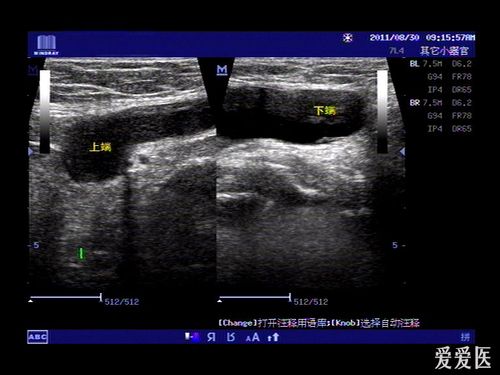

子宫圆韧带囊肿的超声诊断

右侧腹股沟囊性包块---------圆韧带囊肿?

女性腹股沟圆韧带囊肿

nuck囊肿